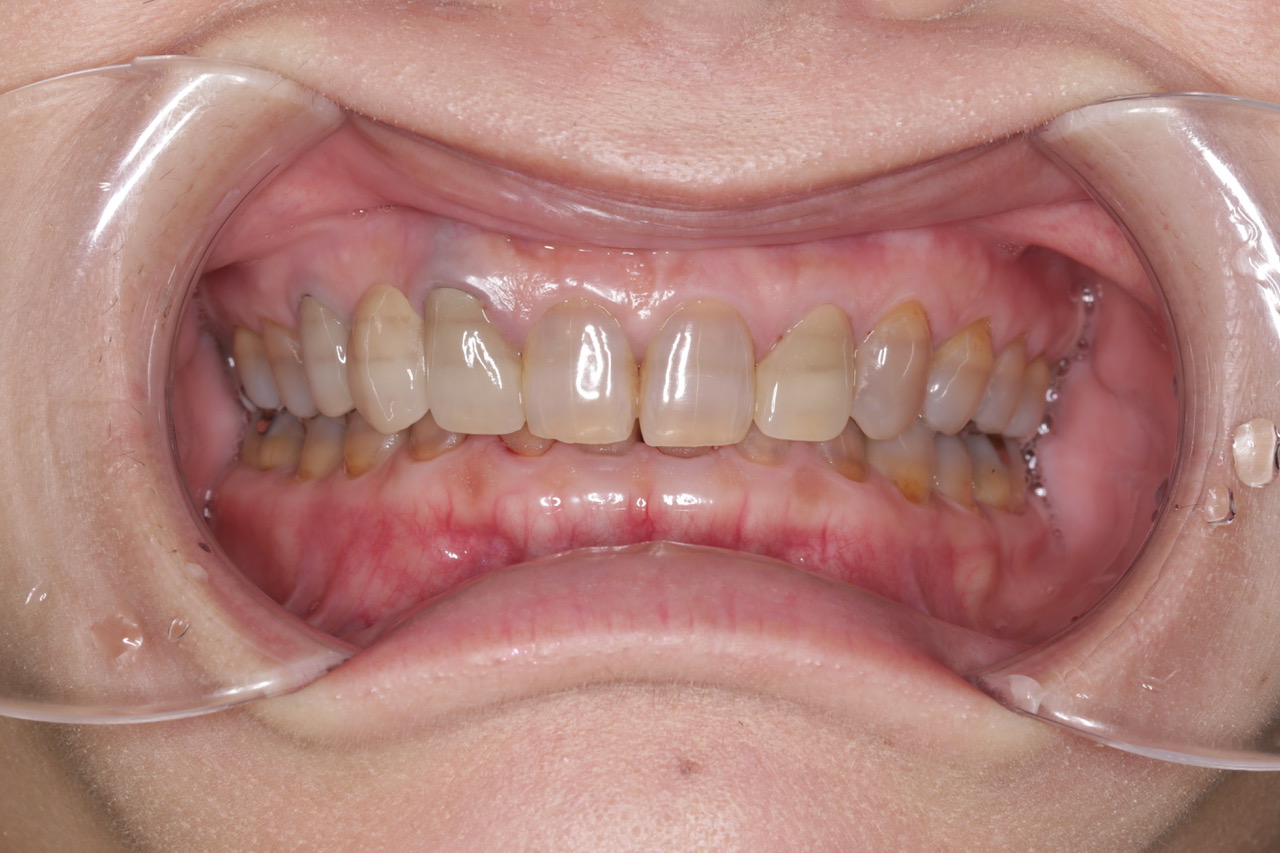

前歯の被せ物をきれいにしたいとのことで来院された患者様(50代・女性)です。

もともと上の左右に硬質レジン前装冠と呼ばれる保険適応で製作された被せ物及びブリッジが装着されておりましたが、周囲歯牙との色調の不一致、被せ物の不適合を認めました。

同時にテトラサイクリン系抗生物質によると考えられる先天性の歯牙の変色が認められました。

今回の患者様はホワイトニングをご希望されなかったため、周囲の歯に合わせた被せ物をジルコニアをベースとして審美性の高い陶材を表層に用いる2層構造のセラミックを当院で製作することとなりました。

<施術後>

歯牙に個性があり何度か試適を行い、ブラッシュアップをした上で、患者様に満足して頂ける被せ物を装着することが出来ました。

当院では院内に歯科技工士が常駐しており、実際に患者様とお会いすることによって皆様にあった被せ物を提供することができます。

また、このような場合には全て仮歯を作成し、形態や咬み合わせを調整し、問題無い事を確認した上で製作しております。